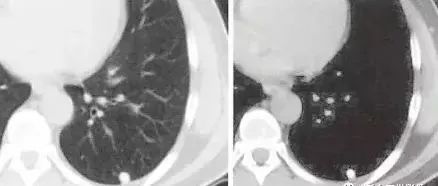

5、肺内淋巴结

肺内淋巴结(IPLN)是指发生在肺四级支气管平面以下、肺实质内的淋巴结,其发生率为1.5%~7.0%。随着CT检查和低剂量肺CT筛查的开展,越来越多IPLN被检出,但由于对其CT表现特点缺乏足够的认识和大宗病例的报道,很多IPLN被疑为恶性结节而行手术切除,不仅增加了医疗负担,还给患者身心带来较大的痛苦。

鉴于IPLN直径较小且主要位于肺周边部位,因此既往文献与本研究均证实其大部分无明显临床症状,多因体检或其他原因行胸部CT检查被偶然发现。有研究发现,在病理在低倍镜下,全部结节均见不同程度的炭末沉积。Shaham等研究认为IPLN以男性、中老年好发,可能与长期吸烟或职业等因素有关,有研究显示长期吸烟是IPLN的重要致病因素,但也有学者认为是吸烟和吸入性粉尘等抗原刺激共同作用的结果。